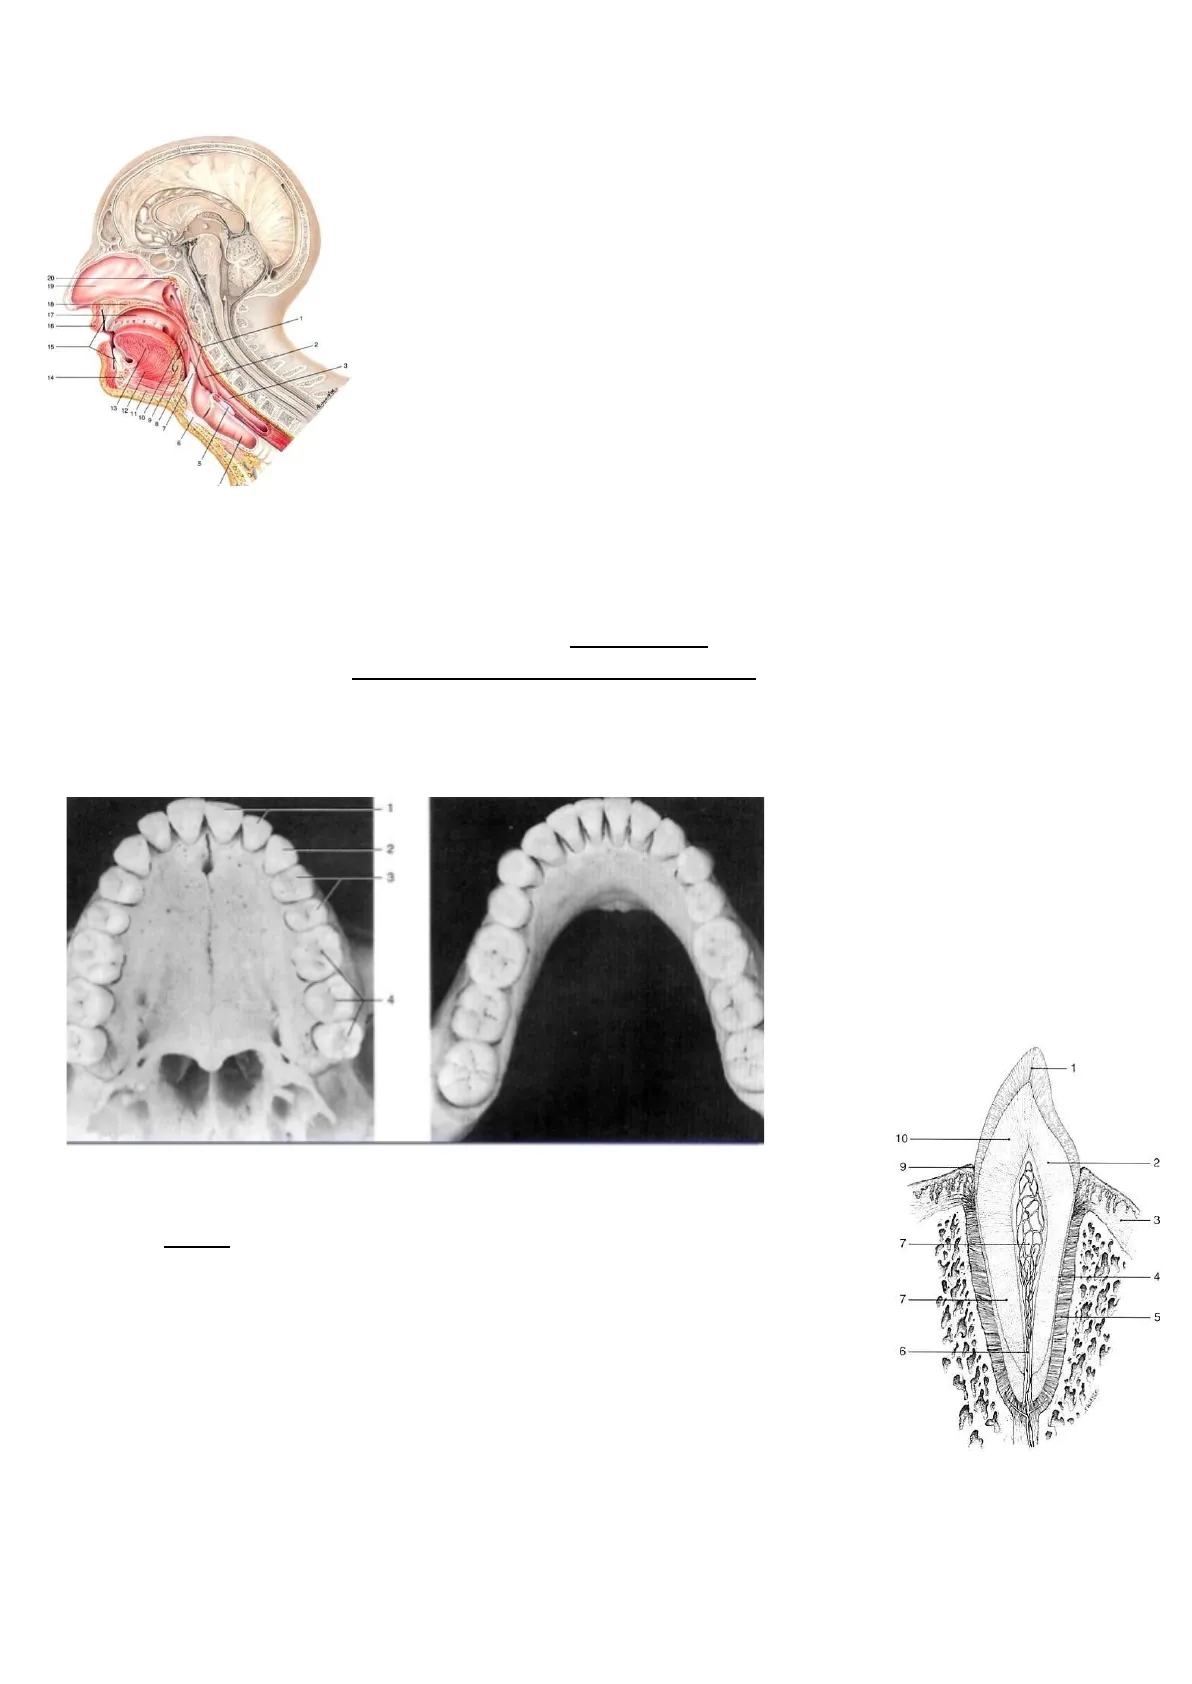

OKL5CAVO ORALE VISTO DA UNA SEZIONE PARA-SAGITTALE SINISTRA 20 4 17 16 14 13 12 11 10 9 8 7 All'interno dell'arcata dentaria e al di sotto del palato vi è la cavità orale propriamente detta. All'esterno di essa c'è uno spazio che è contenuto esternamente dalle guance e dalle labbra, chiamato vestibolo della bocca, che attraverso l'apertura delle due labbra (rima orale) comunica con l'esterno. Al di dietro della cavità orale propriamente detta c'è una porzione ristretta posteriore che è l'istmo delle fauci, quest'ultimo si trova al di sotto del palato molle e al di sopra della radice della lingua.

I denti possono essere studiati tenendo conto delle due emiarcate. Per ogni emi-arcata abbiamo 2 incisivi, 1 canino, 2 premolari e 3 molari. I denti permanenti li descriviamo in opposizione ai denti decidui. Nei denti decidui abbiamo anteriormente la stessa tipologia di incisivi e posteriormente abbiamo 4 molari da latte; sono assenti i premolari.

1 - 2 - 3 Il dente è caratterizzato da una porzione sporgente dalla gengiva (dalla mucosa) chiamata corona, la quale risulta essere lucida poiché è ricoperta da una sostanza chiamata smalto; all'interno di questo smalto abbiamo la dentina che si porta profondamente a formare la parte rigida della radice. Quello del dente è un tessuto mineralizzato, diverso dall'osso. All'interno di esso è presente una cavità chiamata polpa del dente che contiene vasi e nervi, e poi abbiamo un tessuto che unisce la dentina all'alveolo (una cavità ossea) che è chiamata cemento. I denti permanenti sostituiscono quelli da latte intorno ai 7-14 anni, e poi abbiamo gli ultimi molari (denti del giudizio) che hanno un'eruzione tardiva dopo i 17 anni e fino ai 24. 10 9 2 3 7 4 7 5 6

1CAVITA' ORALE PROPRIAMENTE DETTA La papilla parotidea (ghiandola salivare) sbocca (non all'interno del cavo orale propriamente detto) a livello del vestibolo. Intorno alla cavità orale propriamente detta abbiamo l'arcata dentaria (i denti con l'osso che li regge circondati dalla particolare mucosa chiamata gengiva), abbiamo poi un pavimento che è occupato in buona parte dalla lingua e da uno spazio presente sotto di essa chiamato solco sotto-linguale (il pavimento della bocca). Il tetto della bocca è il palato che è suddiviso in: una porzione anteriore che è palato duro, che corrisponde al pavimento osseo del naso, e una porzione posteriore detta palato molle o velo palatino, che è conformato ad una doppia arcata. Questa doppia arcata è presente per via di una sporgenza che si trova al centro chiamata ugola, e il palato molle forma questa arcata che è chiamata arcata glosso-palatina ("glosso" deriva dal latino che è riferito alla lingua, non a caso ci si riferisce all'arcata tra lingua e palato). Dietro l'arcata glosso-palatina c'è un'altra arcata che dal palato molle va verso la faringe, chiamata arcata palato-faringea. 6 1 2 5 3 4 Fra queste due arcate e fra la radice della lingua abbiamo l'istmo delle fauci, nell'istmo (lateralmente) c'è un recesso tra le due arcate dove vi è una superficie irregolare; questa irregolarità è data dalla presenza di alcuni noduli linfatici, cioè lì c'è un tessuto linfatico (linfociti), che sporgono in questo sito particolare e queste sporgenze sono le tonsille palatine (in generale tonsille= cellule di difesa + mucosa).